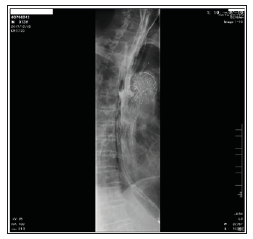

TEVAR is associated with better early and late outcomes than open repair, including lower perioperative morbidity and mortality and has changed the therapeutic paradigm for thoracic aortic lesions. This difference in outcomes has led to TEVAR replacing open repair as the procedure of choice for most patients with TAAs and suitable anatomy [6]. TEVAR has recently gained popularity as an emergent treatment for AEF due to better perioperative outcomes and safety than open surgery in unstable patients. However, TEVAR does nothing to address the issue of the defect in the digestive tract, which leaves these patients at high risk of AEF recurrence and/ or stent graft infection and leads to a high rate of re-intervention. Re-intervention after TEVAR is reported in up to 3.8% of patients independently of the type of endograft implanted (Figure 2). Although re-intervention is often endovascular, patients with serious complications (including device failure, endograft migration, endograft infection, endoleak, AEF or aorto-bronchial fistula and retrograde type A dissection (RTAD) that may lead to aneurysm rupture) often ultimately undergo conversion to open surgery [3,7].

Figure 2: Oesophagography was performed before the second surgery. Apparent contrast agent leakage from the oesophagus into the DsAo during swallowing confirmed SAEF.